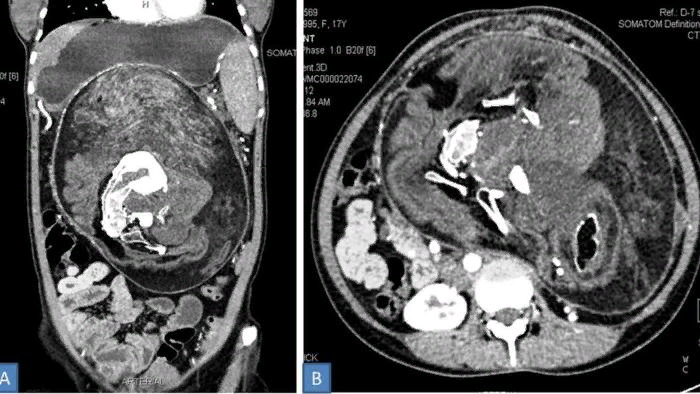

В течение почти двух десятилетий молодая женщина из Индии жила с одним из самых редких и необычных медицинских состояний. В животе пациентки находился мешок, содержащий её "близнеца". У последнего имелись волосы, зубы и даже позвоночник. Что удивительно, сама девушка о нём не подозревала. Такое состояние известно как утробный плод в плоде. Речь идёт об аномалии, при которой внутри организма одного плода имеется масса тканей, напоминающая плод. Считается, что такая аномалия возникает на раннем этапе монозиготной беременности близнецами. В это время оба плода имеют общую плаценту, и один из них "оборачивает" собой другого. В итоге завёрнутый внутрь эмбрион становится "паразитом". При этом у него не развиваются мозг и нервная система, и он способен выжить только за счёт жизнеспособного близнеца.